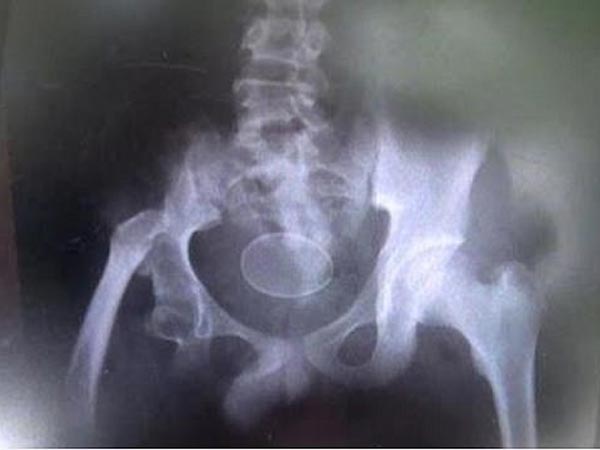

एक्स रे तक में दिखाई दिया अंडा

अकमल और उसका परिवार अपने इस दावो के साथ एक हॉस्पिटल भी पहुंचे जहां अकमल का एक्स-रे भी करया गया, एक्स-रे में अंडा भी नज़र आ रहा है, लेकिन डॉक्टर्स को अब भी कुछ समझ नहीं आ रहा है।